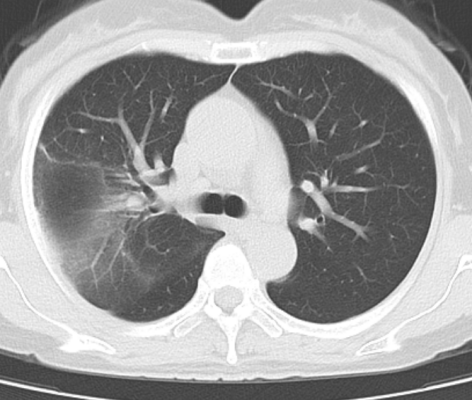

遂至我院感染科门诊就诊,完善肺部CT提示右上肺大叶性肺炎、双侧胸腔积液。入院后,主任查阅了患者的检查、检验报告单,并了解到其家中饲养几十只鸽子后,找出了她反复高热的元凶——鹦鹉热衣原体。

经积极治疗,李女士症状逐渐好转,出院前复查肺部CT,肺部病灶明显吸收。